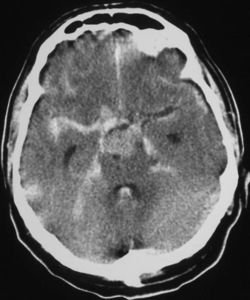

CT scan of the brain showing subarachnoid hemorrhage as a white area in the center

نزف تحت العنكبوتية Subarachnoid hemorrhage (SAH)، أو subarachnoid haemorrhage، هو نزيف داخل الحيز تحت العنكبوتية subarachnoid space المحيط بالمخ، وهي المنطقة بين الغشاء العنكبوني arachnoid membrane والأم الحنون pia mater. فيه يحدث النزف ضمن الطبقة السحائية العنكبوتية. وأكثر الأسباب شيوعاً هو رضوض الدماغ، أما حالات النزف غير الرَّضِّيّ فتنتج عادة من انفجار أم دم aneurysm (وهي توسع كيسي غير طبيعي في شريان أو أكثر). ومن الأسباب الأخرى التشوهات الشريانية الوريدية، والتهاب الأوعية، وتسلخ الشرايين، واعتلالات التخثر، وخثار الجيوب الوريدية، وفقر الدم المنجلي، وتمزق شريان سطحي صغير. ويبقى السبب مجهولاً في نحو 14ـ22% من الحالات. وفيما يأتي نبذة عن النزف تحت العنكبوتية الناتج من أمهات الدم لكونه الأهم بينها.[1]

يعتمد بصفة رئيسة على تصوير الدماغ، ومن أكثر طرق التصوير استعمالاً التصوير الطبقي المحوري (الشكل3)، وبدرجة أقل المرنان المغنطيسي. وجدير بالذكر أن تصوير الدماغ قد يخفق في إظهار النزف في نحو 5% من المرضى، وفي هذه الحالة يمكن اللجوء إلى استقصاء آخر هو البزل القطني للسائل الدماغي الشوكي. وتظهر دراسة السائل وجود أعداد كبيرة من الكريات الحمر، مما يثبت حدوث النزف.